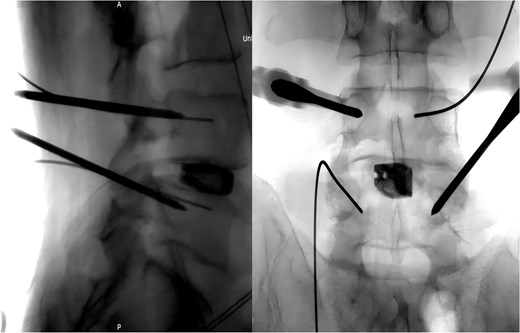

During the surgery, after sufficient decompression at the L4/L5 level and placement of the interbody fusion cage, a complication occurred during the percutaneous pedicle screw insertion. Intraoperative G-arm fluoroscopy confirmed the correct trajectory of the pedicle screw, established by the guidewire and puncture needle, and the pedicle screw was inserted along the established pathway (Fig. 2). However, after removing the guidewire, fluoroscopic imaging revealed that a portion of the guidewire had broken near the anterior margin of the left L5 pedicle screw (Fig. 3). The fracture likely occurred during screw insertion or tightening, which subsequently displaced the broken guidewire toward the anterior vertebral margin. Given the proximity of the fractured guide wire to the anterior vertebral margin, along with the risks of future migration causing injury to adjacent tissues or vessels, as well as the potential for local infection or pain, the decision was made to remove the fractured guidewire after obtaining informed consent from the patient’s legal representative.

Intraoperative fluoroscopic confirmation of guidewire breakage.